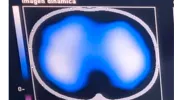

Imágenes de tomografía que se toman para analizar el desempeño de la fisioterapia con el incentivo de re-expansión pulmonar. El área de color azul-blanco representa el volumen del pulmón en un corte transversal, visto desde arriba, cuanto mayor aire llega a los pulmones se expande el pulmón y llega aire a zonas al pulmón que originalmente no se utilizaban.

Cuando inició la pandemia se dio conocer que los pacientes estaban desarrollando fibrosis pulmonar, y se reportó que algunos ya recuperados presentaron una reducción de su capacidad respiratoria entre el 20% y el 30%, incluso las tomografías pulmonares mostraron imágenes de vidrio esmerilado.